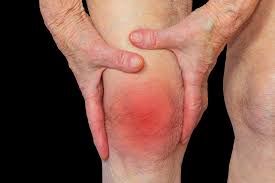

날씨가 급격히 추워지면서 관절통증을 호소하는 사람들이 늘고있다고 한다.

특히 통증이 심한 류마티스관절염은 자가면역질환 중 하나로, 관절에 만성적 염증과 통증을 일으켜 결국 비가역적인 관절손상을 일으키는 질환이라고 한다.

류마티스관절염은 초기에는 피로감, 미열, 전신 근골격 통증이 동반될 수 있고, 손가락, 발가락 등의 관절 마디가 붓는다고 한다.

병이 진행되면 다발성으로 여러 관절이 동시에 붓고, 자는 동안 악화돼 아침에 일어나면 한 시간 이상 뻣뻣하고 부기가 가라앉지 않는다고 한다.

원장은 “특히 겨울철에는 증상이 더욱 심해지는 경향이 있는데, 기온이 내려가면서 관절 주위의 근육이나 인대, 힘줄들이 추위로 인해 수축되어 더욱 뻣뻣해지기 때문이다라고 한다.